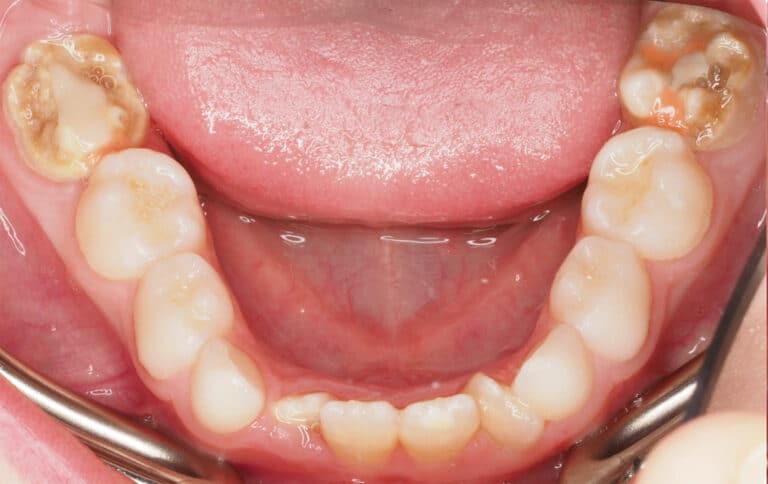

Here’s another example of well-timed treatment to address chalky teeth. In this case, both of the lower 6 year old molars were chalky teeth.

With careful planning, those teeth were removed at the right time, allowing the 12-year-old molars to move into place. And with wisdom teeth still to come, this patient now has a strong, healthy set of molars in the right positions, without any lingering issues from chalky teeth.

Notes: In addition to extraction the the lower first molars (and awaiting eruption of lower second molars), patient’s crowding was treated with upper and lower braces for 20 months. Results will vary depending on patients’ individual circumstances. Outcomes shown are only relevant for this patient and do not necessarily reflect the results other patients may experience.